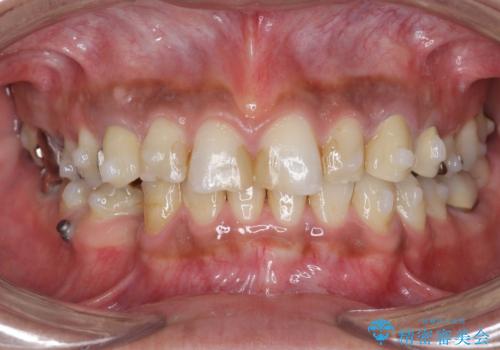

- 長年虫歯の治療を受け続けたことで銀歯・コンポジットレジン修復だらけになってしまい、今後の見た目や歯を大切にするためにセラミック治療矯正治療を希望され来院されました。

マイクロスコープを用いた精密根管治療やセラミック治療、マウスピース矯正治療を一つの医院で行うことのできる当法人ならではの総合歯科治療を実践していきます。

歯並びを整えたことで、歯ブラシのしやすさが向上し見た目も銀歯を全て除去したことで大きく改善して大変満足いただくことができました。